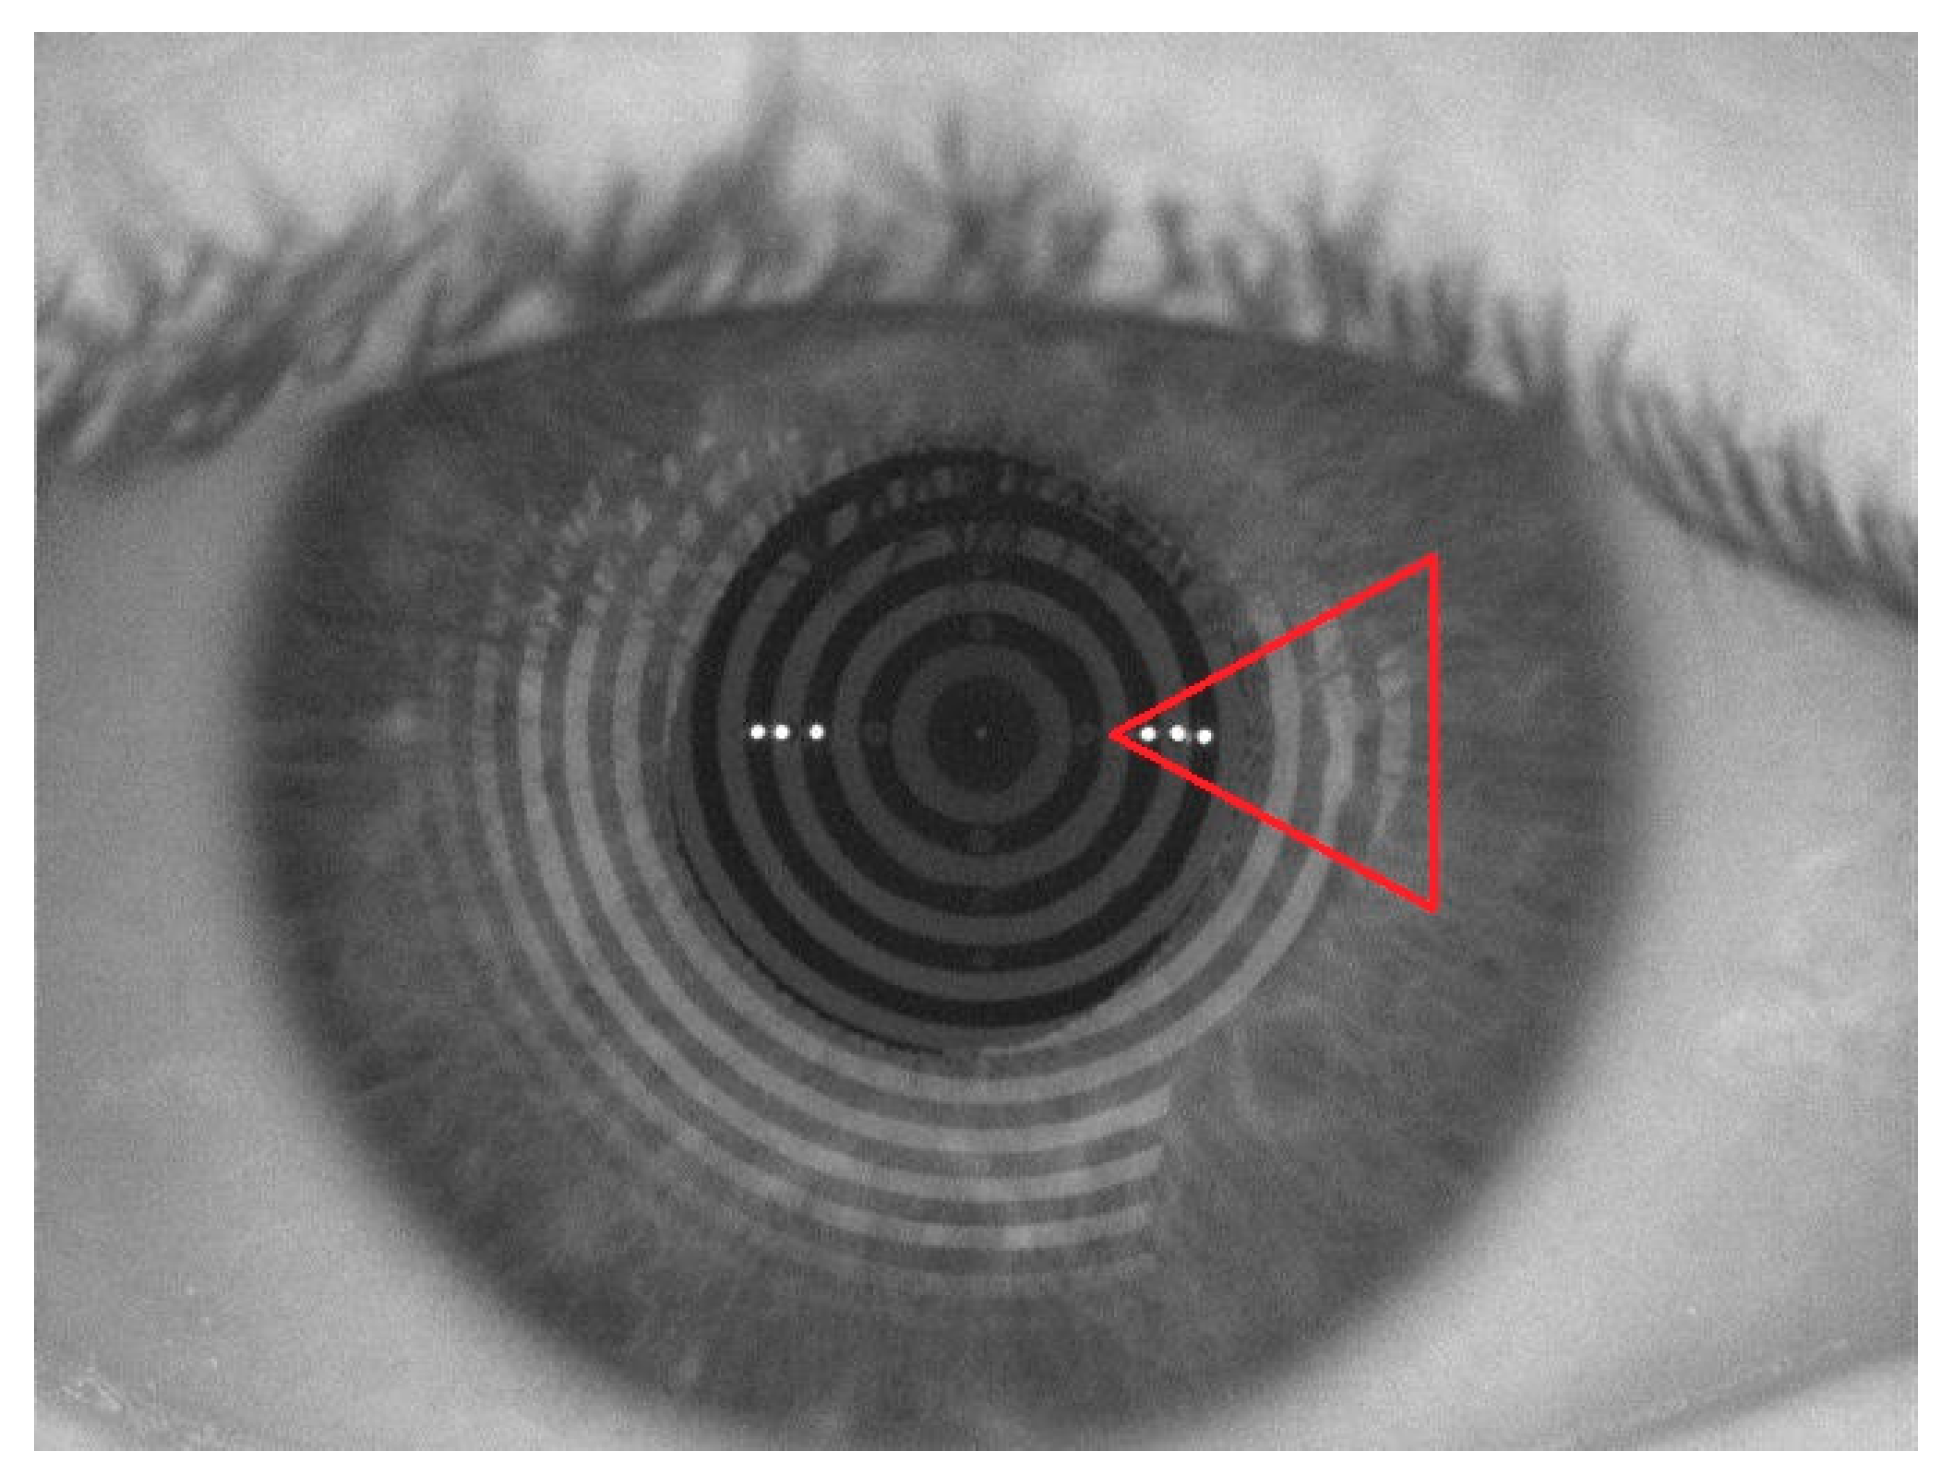

3.4. Ocular Surface Permanence Studies in Healthy Volunteers